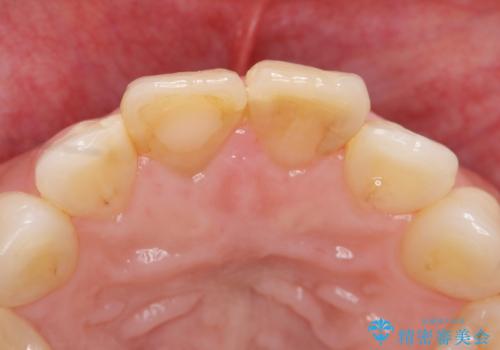

天然歯を再現したリアルな仕上がりに満足いただくことができました。

オールセラミッククラウン スペシャルプランは細やかな色調の再現に優れ、目立つ前歯の審美的な仕上がりがより達成されやすいプランです。